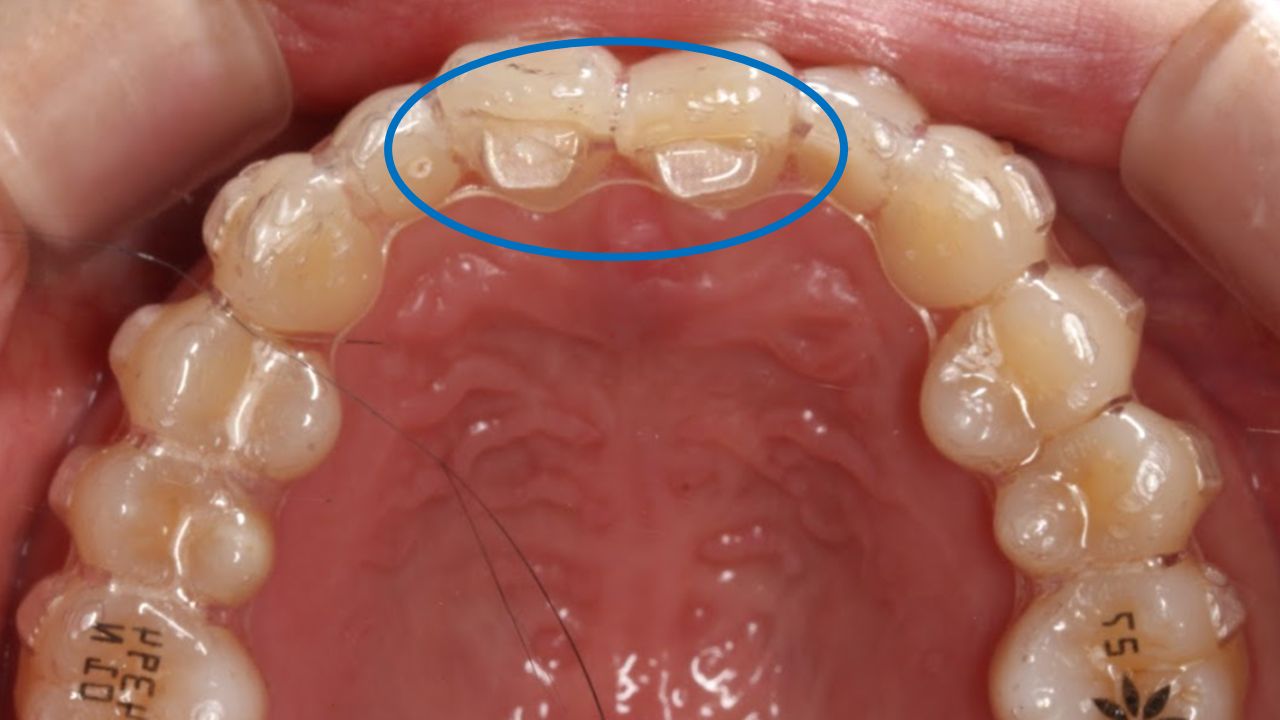

インビザラインのバイトランプは、上顎マウスピースの前歯裏側に付与される3mmほどの小さな突起で、ほとんどが上の前歯2〜4本に設置されます。特に過蓋咬合(かがいこうごう)の治療の際に使用されます。

バイトランプは上の前歯の裏側に付与されるため、一般的には目立ちません。口を開けた状態でも外側からは見えにくい構造になっています。また、歯の表面に歯科用レジンで装着されるアタッチメントとは違い、透明なマウスピースの一部として形成されており、審美的な影響は少ないと言えます。

【バイトランプ使用時の正面観・前歯部あおり】